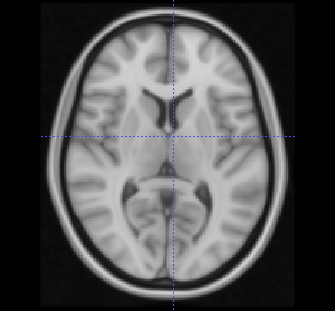

例如,我在3D阵列图像上运行了带有7个类和128个桶的threshold_multiotsu,即尺寸为182x182x218 (磁共振成像分析的标准模板)的1mm分辨率的MNI152 T1-w模板。在我的桌面计算机上,经过的时间大约是3分钟。

原始MNI T1-w模板